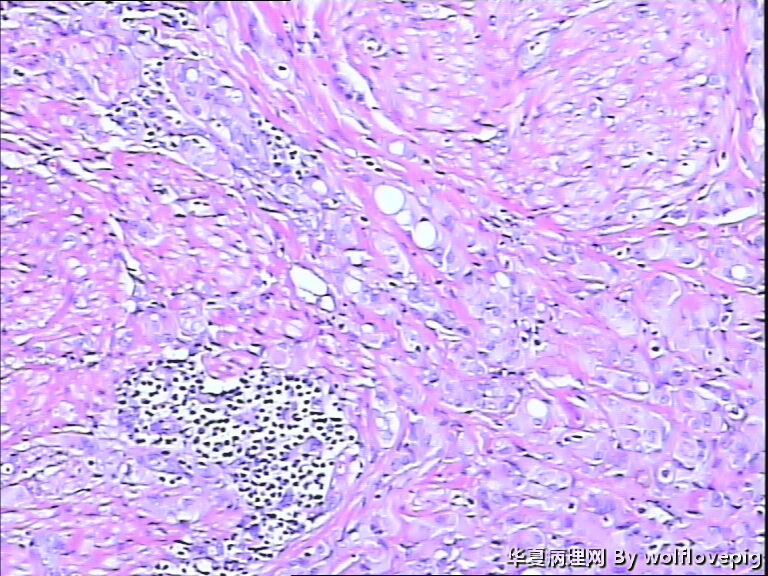

男,60y,左阴囊包块6月,位于附睾尾与睾丸之间,无粘连。灰白结节一个0.7*0.3*0.3,切面灰白、实体 、质韧。

典型的腺瘤样瘤

同意腺瘤样瘤